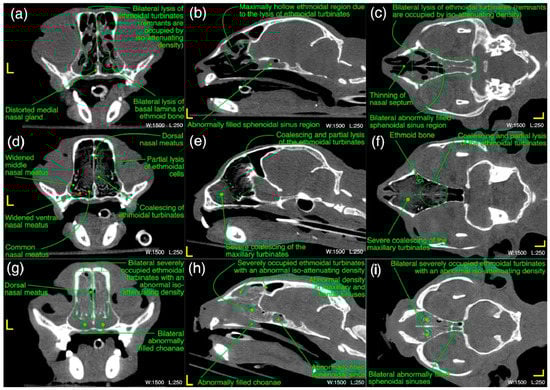

In ethmoidal region, a bilateral moderate to severe lysis of the turbinates including basal laminae of the ethmoid bone [Figure 10a–c] in 55% (n = 12) cases was a predominant finding. Severe infiltration of the bilateral nasal passages and choanae of this region with an abnormal space occupying soft tissue/fluid density [Figure 10g–i] were seen in 32% (n = 7) of the cases. Distorted medial nasal gland [Figure 10a], bilateral moderate thickening of the ethmoidal turbinates with/without hyper-attenuation and partial lysis of the nasal septum [Figure 10c] were recorded in 27% (n = 6), 18% (n = 4) and 9% (n = 2) cases, respectively. As concerned with the localized findings of this region, here also bilateral abnormalities (Figure 14) were predominant findings and recorded in 64% (n = 14) cases and unilateral left or right side was not affected in any case.

Figure 10. (ai) A variety of computed tomographic changes of ethmoidal region are labeled for pathologies related to acute/chronic infectious respiratory disease signs in Cats 1, 6 and 18. Window, level and laterality are also labeled for each section.